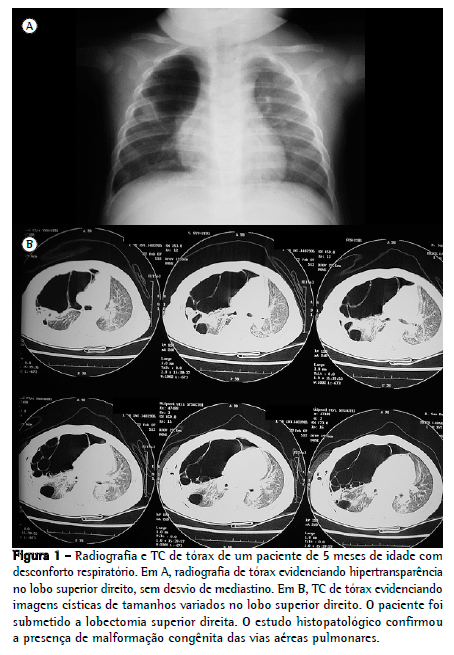

Enfisema lobar congênito

O enfisema lobar congênito, também conhecido como hiperinsuflação pulmonar infantil, é uma malformação pulmonar rara que ocorre apenas uma vez a cada 30 mil nascimentos. A principal característica dessa malformação é a hiperinsuflação de um lobo pulmonar por aprisionamento aéreo, resultando em distensão do lobo e provocando a compressão dos demais.

Em alguns casos o enfisema lobar congênito é assintomático, mas já é observado que a grande maioria dos indivíduos apresenta sintomas antes dos seis meses de vida – destes, 50% são diagnosticados com a malformação no primeiro mês. O enfisema pode ser diagnosticado no período pré-natal pela ultrassonografia, o que torna possível a diminuição espontânea de volume e até mesmo o desaparecimento das lesões.

Essa malformação é duas vezes mais comum em homens do que em mulheres e acomete com mais frequência o lobo superior esquerdo. Geralmente, o tratamento indicado é através da cirurgia, sendo ela a lobectomia por toracotomia ou videoassistida.